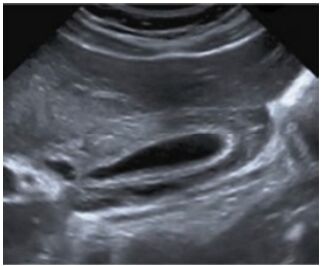

27.下圖為何種檢查、那一側的集尿系統有問題?

(A)intravenous urography(IVU)、left (B)intravenous urography(IVU)、right (C)voiding cystourethrography(VCUG)、left (D)voiding cystourethrography(VCUG)、right